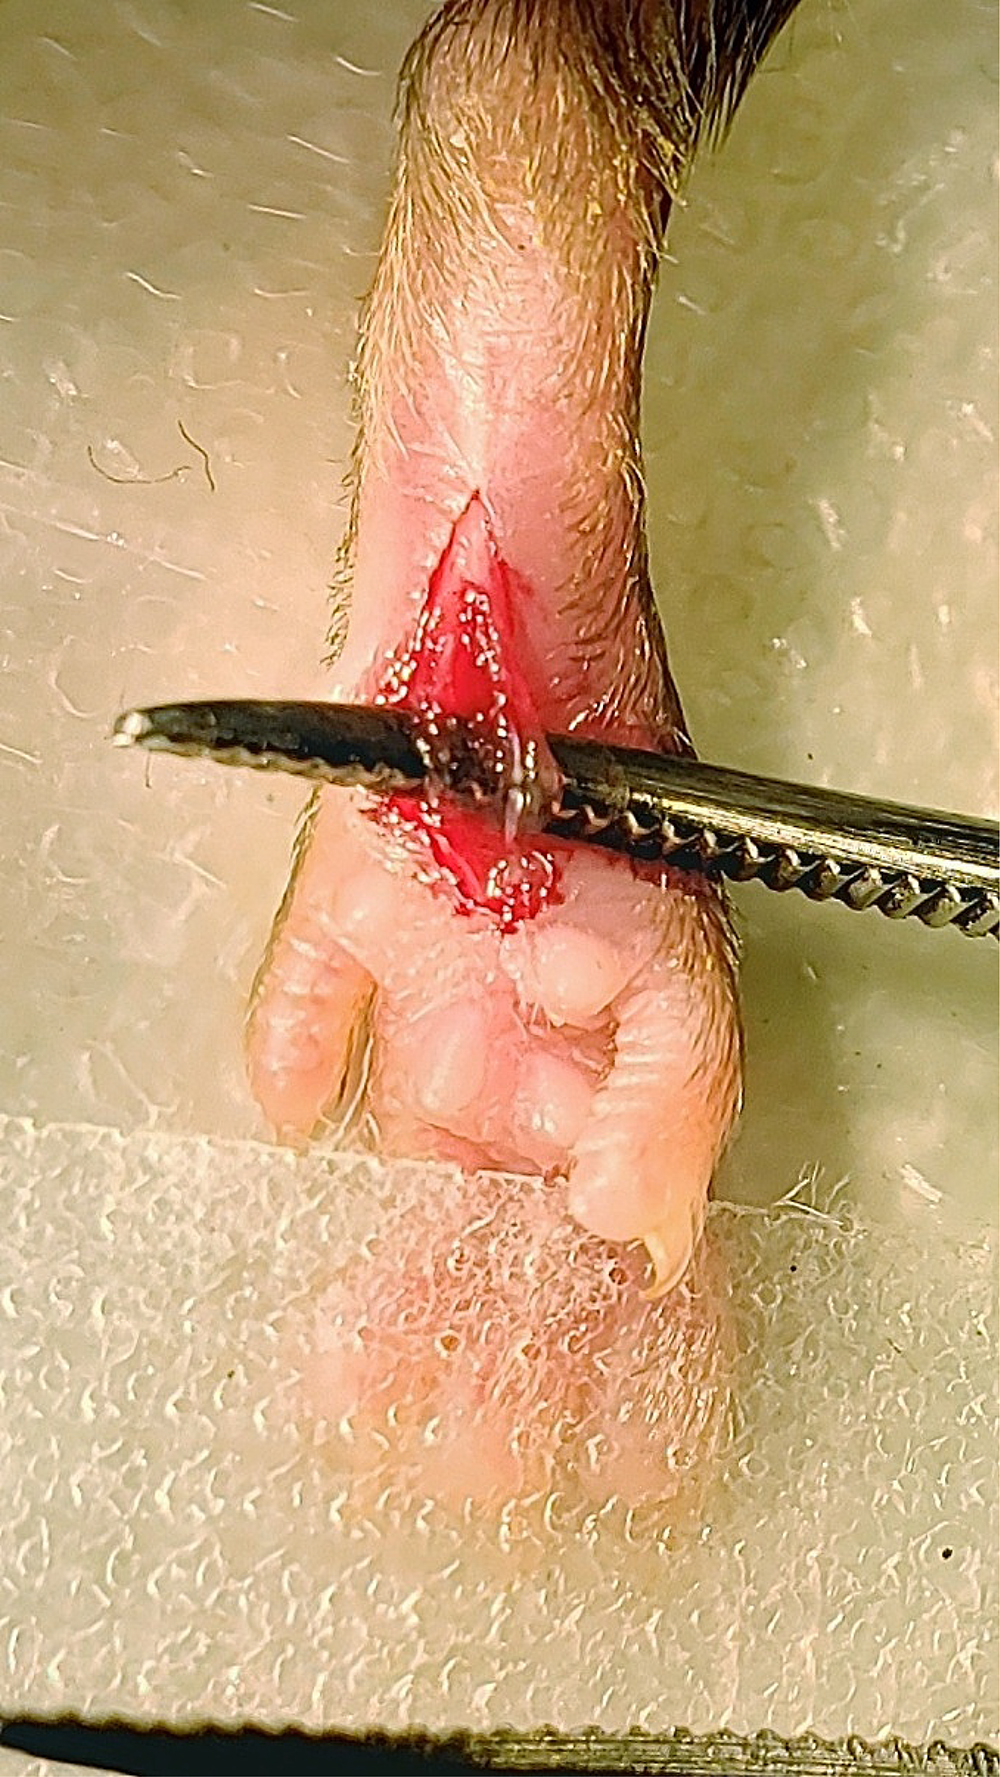

Figure 5. Cutaneous incision. A 5 mm longitudinal incision was made with a No. 11 scalpel. - Spread the skin away from the flexor digitorum brevis muscle with the forceps. Elevate the flexor digitorum brevis muscle by inserting one end of the curved forceps underneath the lateral edge of the flexor digitorum brevis muscle and pushing the forceps through to the medial side of the muscle (Figure 6).

Figure 6. Elevation of flexor digitorum brevis muscle. Curved forceps were inserted under the flexor digitorum brevis muscle to elevate the muscle. - Make a longitudinal incision with the scalpel through the entire belly of the muscle from the origin and insertion taking care not to sever the muscle completely from the origin and insertion, making sure to cut the belly of the muscle into two halves (Figure 7).

Figure 7. Muscle incision. A longitudinal incision was made through the muscle belly of the elevated flexor digitorum brevis muscle from proximal to distal ends of the cutaneous incision. - To suture the wound, remove the curved forceps from underneath the muscle and elevate the edges of the skin surrounding the wound with forceps. Close the wound by putting two sutures in the skin (but not muscle) approximately 2 mm apart using 5-0 nylon sutures and a hemostat (Figure 8).